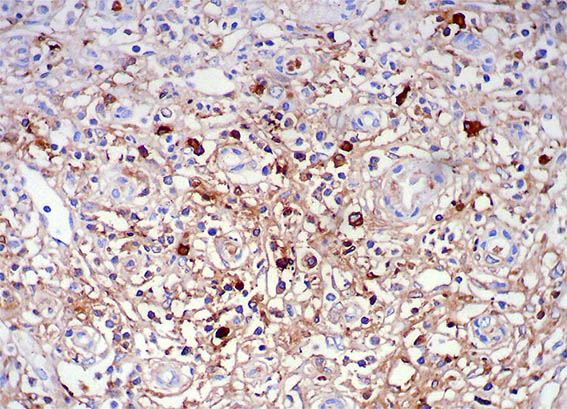

Figura 12. Inmunohistoquímica para IgG4, X400.